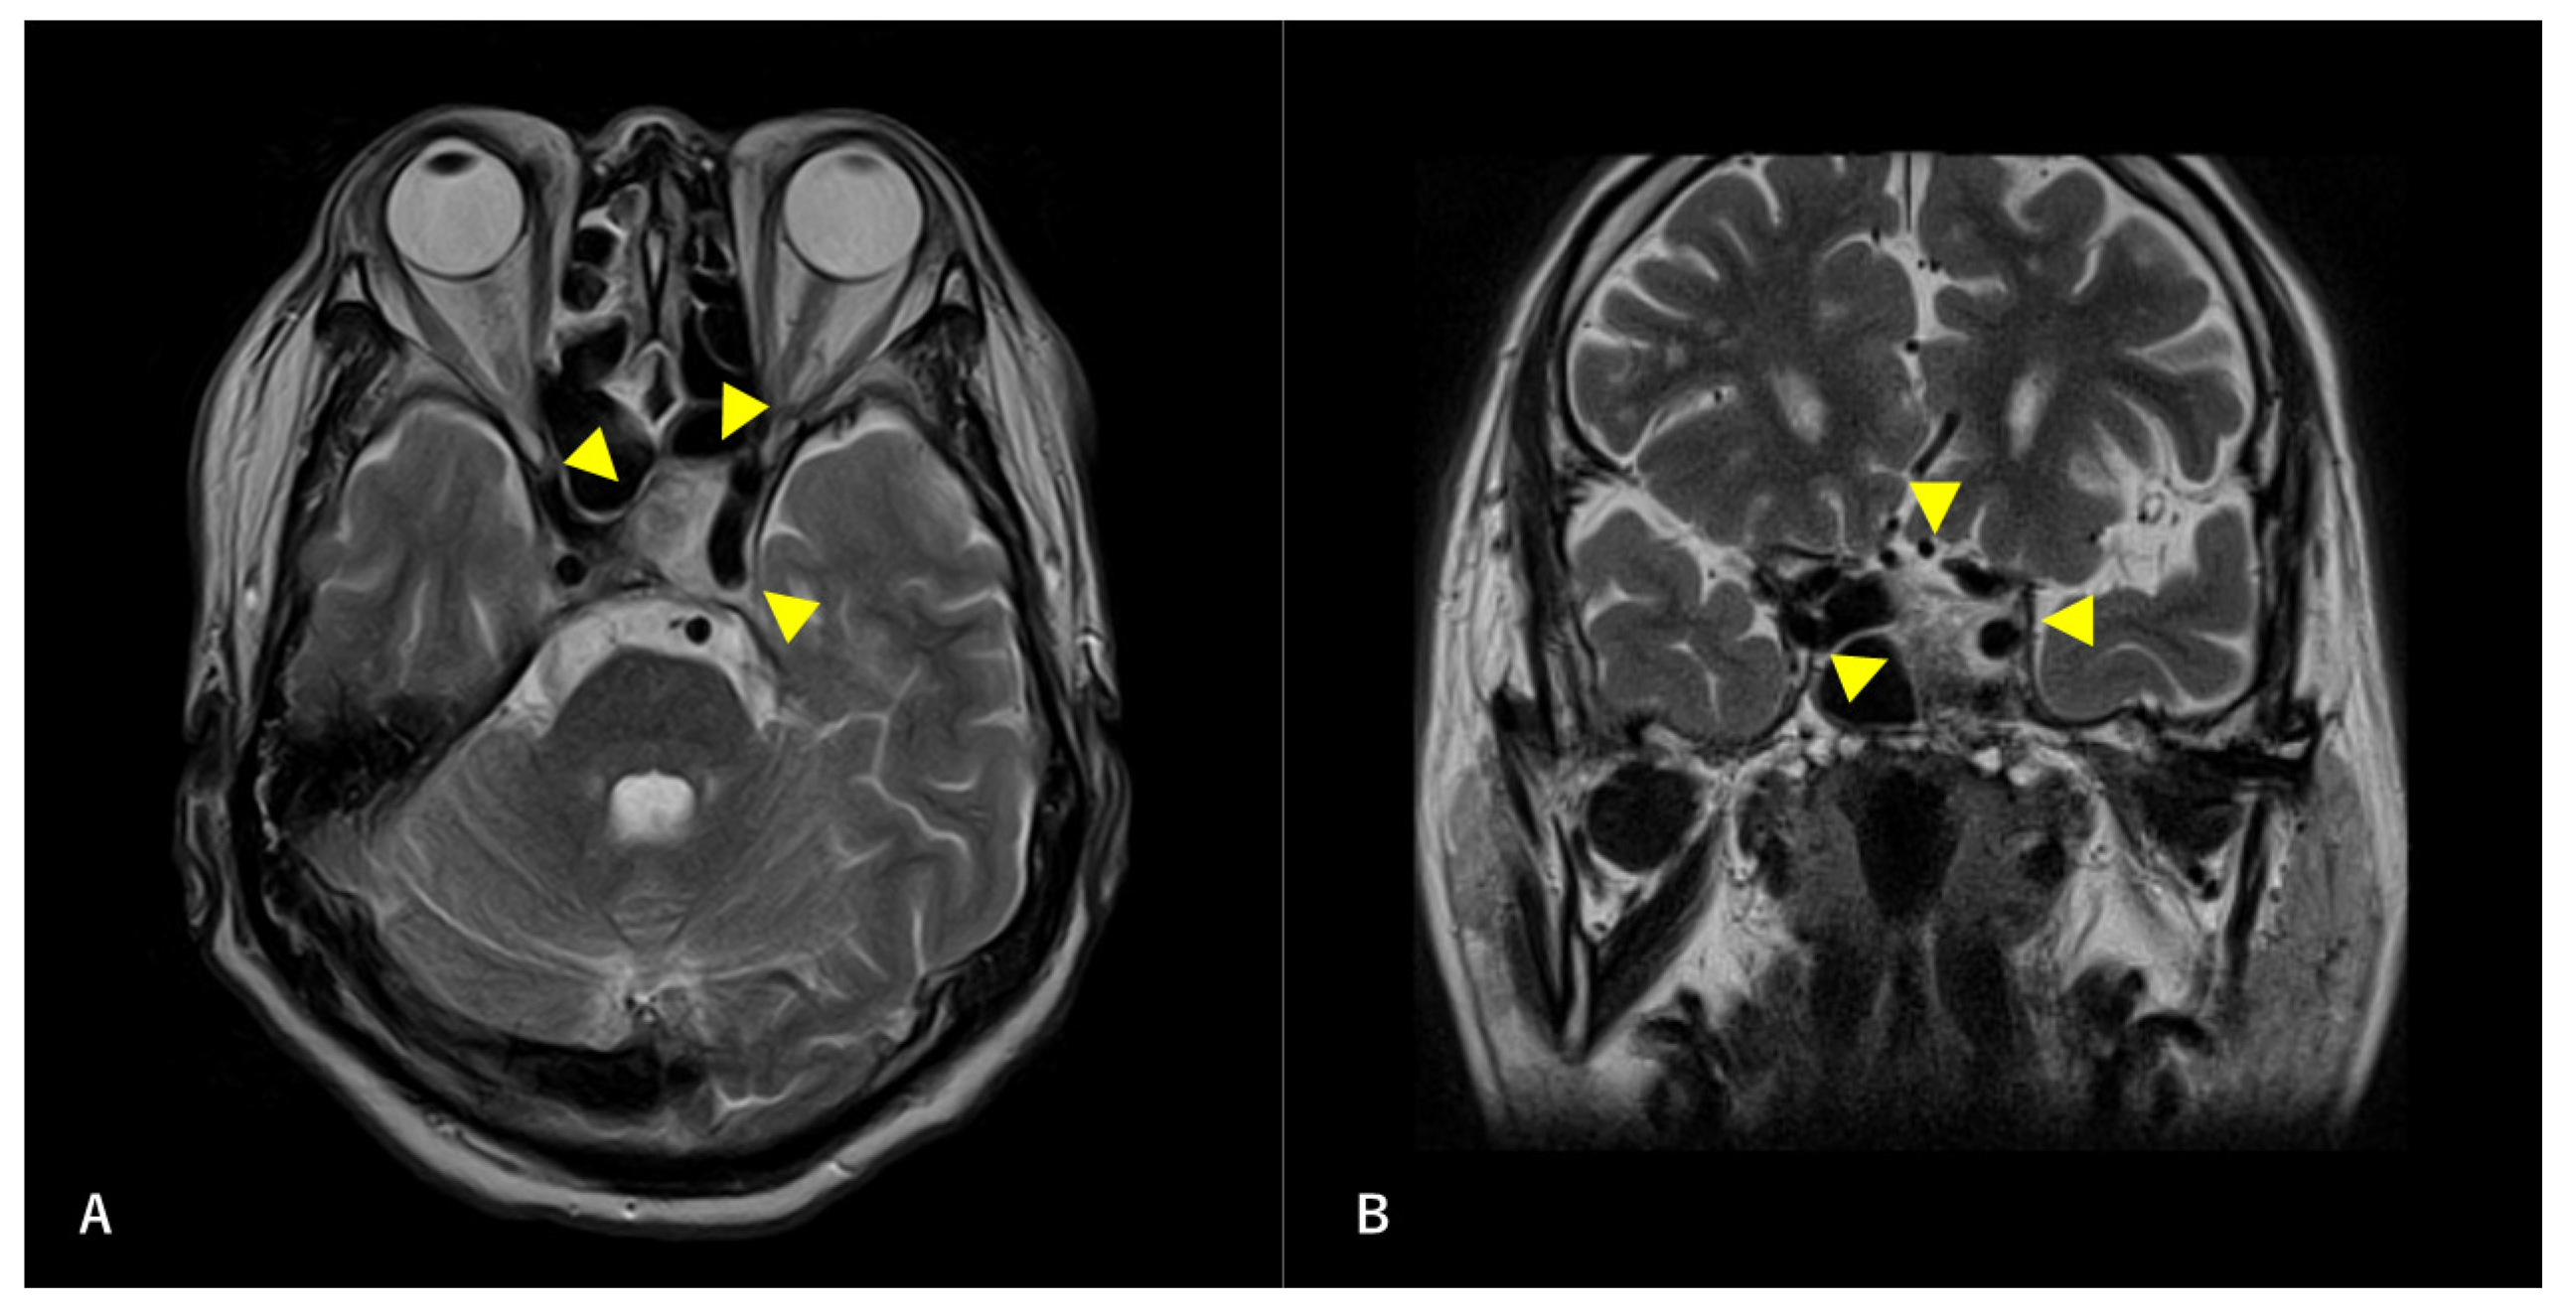

Figure 2. Preoperative T2-weighted magnetic resonance image (MRI) findings. Axial section (A) and coronal (B) images are shown. A high-intensity mass is observed in the left sphenoid sinus. The ICA is surrounded by a mass. Arrowheads indicate tumors.